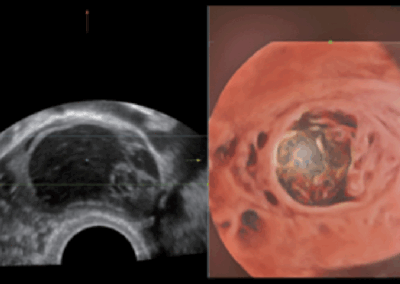

Consona N9

El Consona presenta soluciones nuevas y concretas, que lo ayudarán a realizar diagnósticos fluidos para amplios tipos de pacientes de manera eficaz.

No importa que su rutina sea en hospitales, clínicas, o que esté perfeccionando sus habilidades, en esta serie encontrará herramientas muy potentes y disponibles para mantenerse a la vanguardia.